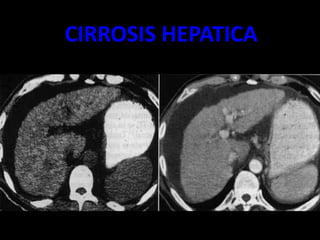

CIRROSIS HEPATICA

• Volumen hepático disminuido, bordes ondulados

• Parénquima con hiperecogenico, formado por ecos gruesos y

con atenuación posterior.

• VP incremento de diámetro, por encima de 14mm.

• VSH disminuidas de diámetro.

• VCI sin latido trasmitido

• Hipertrofia del segmento I, con hipoecogenisidad

• Ascitis

• Esplenomegalia

Ascitis

Bordes ondularos

irregulares

Lobulo hepatico

derecho diminuido

de tamaño

– EXISTE UNA DESTRUCCION MASIVA DE LOS

HEPATOCITOS , POR TANTO HAY UNA PERDIDA

DE LA ARQUITECTURA DE LA FORMA HEPATICA.

– TIPOS LAENNEC

– POSNECRÒTICA

– BILIAR ( SECUNDARIA A LA COLECISTITIS

INTRAHEPATICA CRONICA)

– INFILTRACION GRASA

– HEPATOMEGALIA

– FIBROSIS

– HIPERTENSIÒN PÒRTAL

– CONTORNOS LOBULADOS E IRREGULARES .

– ATROFIA DEL LOBULO DERECHO E HIPERTROFIA

DEL IZQUIERDO.(AL)

– ASCITIS.